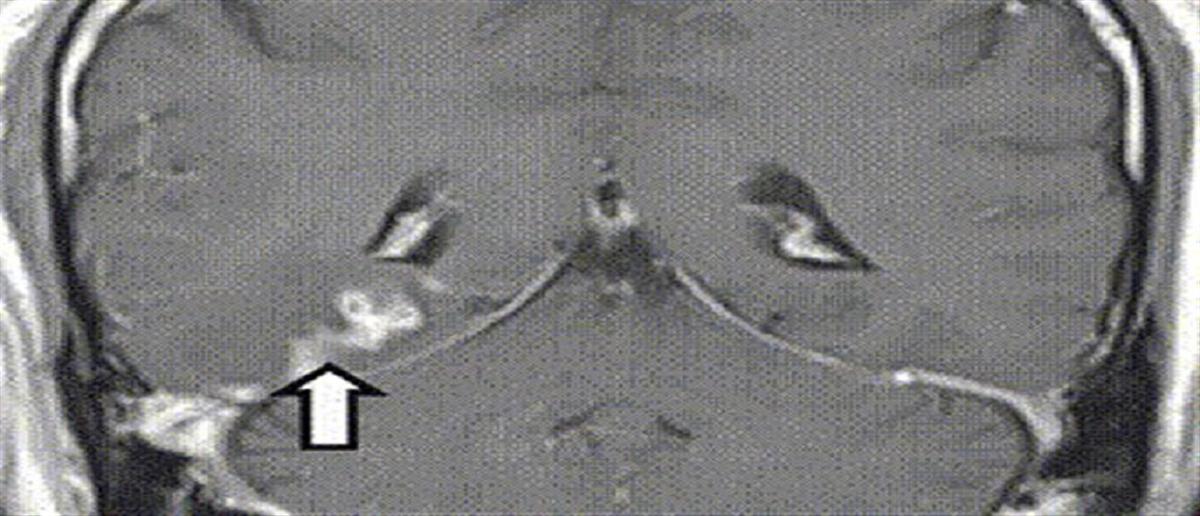

Οι μαγνητικές τομογραφίες έδειξαν ανωμαλία στο δεξί ημισφαίριο, δεν έδειξαν όμως όγκο.

Όμως οι μαγνητικές που έκανε ο 50χρονος τα επόμενα τέσσερα χρόνια έδειξαν την ανωμαλία να κινείται σε απόσταση πέντε εκατοστών και να περνά στην αριστερή πλευρά του εγκεφάλου.